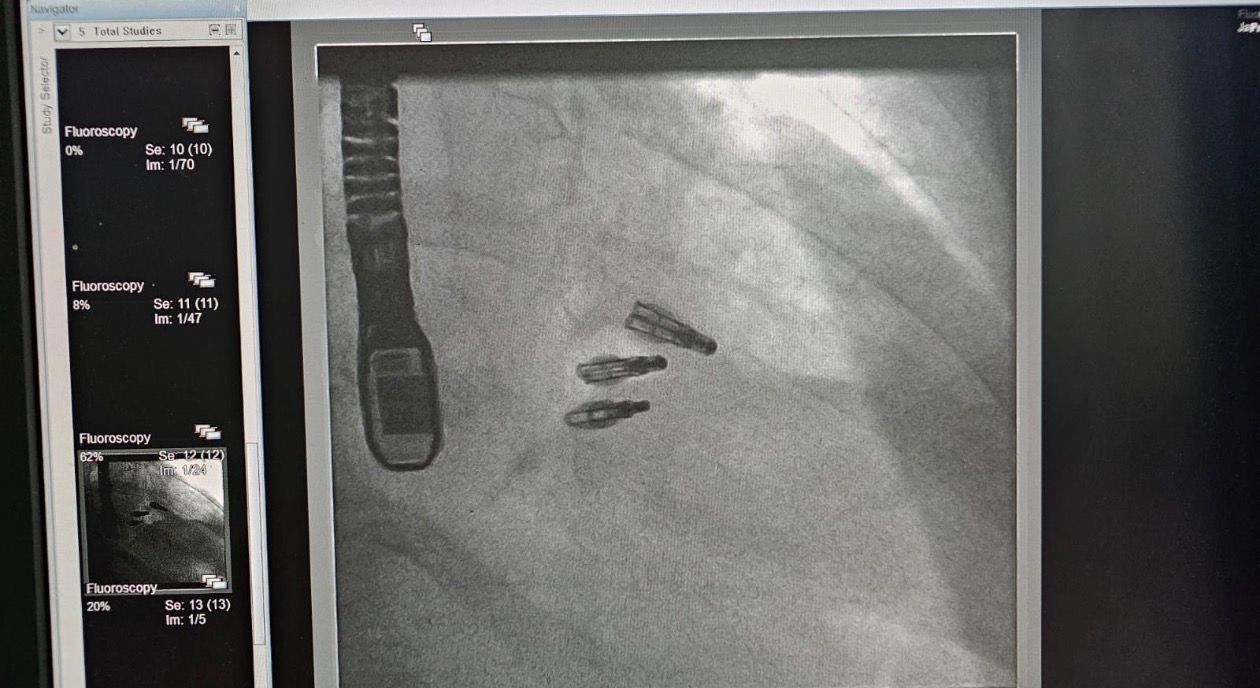

حقق مستشفى القوات المسلحة بالجنوب انجازاً طبياً نوعياً بعد نجاح فريق طبي متخصص بمركز الأمير خالد بن سلطان لأمراض وجراحة القلب في إجراء ثلاث عمليات دقيقة لثلاثة مرضى لإصلاح الصمام ثلاثي الشرفات عن طريق القسطرة القلبية دون الحاجة إلى تدخل جراحي مفتوح وذلك باستخدام أحدث التقنيات التداخلية المتقدمة.

وأوضح الدكتور صالح بن عبدالله الشهري، مدير مركز الأمير خالد بن سلطان لأمراض وجراحة القلب أن هذه الإجراءات أُجريت باستخدام تقنية حديثة تُعد من أحدث ما توصل إليه الطب في هذا المجال وتمثل الأولى من نوعها في المنطقة الجنوبية، حيث تم استخدام مشبك الصمام ثلاثي الشرفات كحل تداخلي متقدم لعلاج القصور الوظيفي للصمام بما يسهم في تحسين جودة حياة المرضى وتقليل المخاطر المصاحبة للجراحة التقليدية.

من جانبه، بيّن الدكتور عبدالله اليوسف استشاري القسطرة القلبية أن التدخلات أُجريت عبر القسطرة القلبية من خلال الوريد الفخذي وباستخدام مشبك مخصص لإصلاح الصمام ثلاثي الشرفات، وقد تكللت العمليات الثلاث بالنجاح ولله الحمد حيث غادر المرضى المستشفى وهم يتمتعون بصحة جيدة وتحسن ملحوظ في حالتهم الصحية دون تسجيل أي مضاعفات تُذكر .